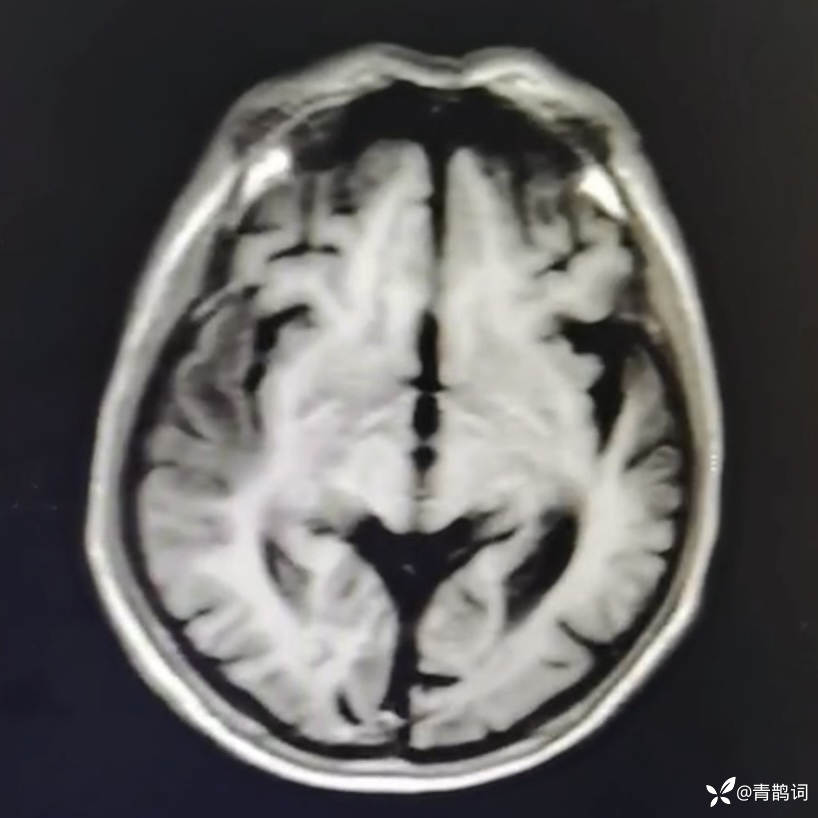

乐痴于医等 2人推荐简要病史:42岁男性,记忆力下降及听力下降一年余。既往体健,否认前驱感染病史。否认家族史。三个月前就诊于当地医院,自述腰穿脑脊液乳酸增高。现就诊于我院,查体记忆力下降,计算力下降,定时定向差,吟诗样语言。完善磁共振如下:

DWI:

2.患者小脑萎缩严重,和大脑半球的病灶之间有无关系?能否用一元论解释?